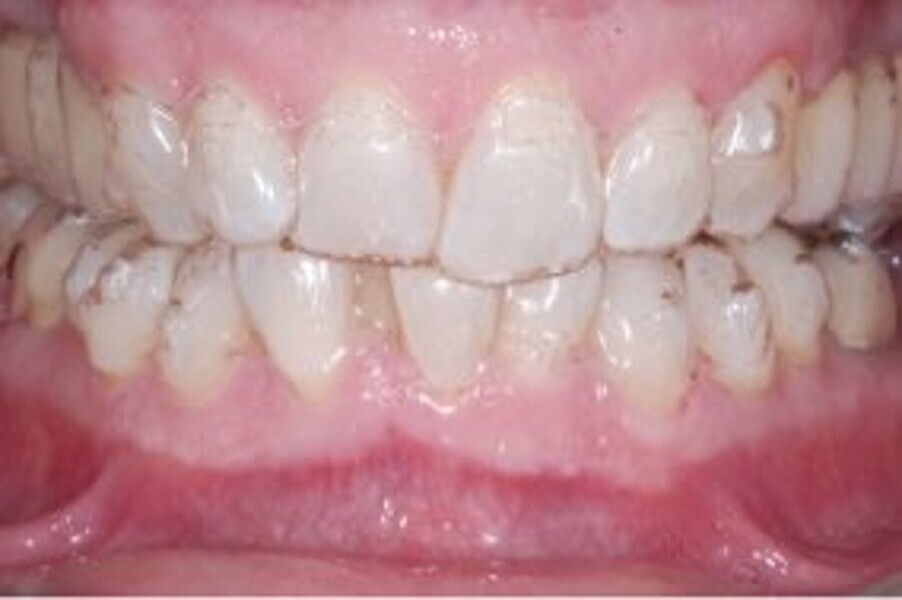

Le motif principal de consultation de ce patient âgé de 37 ans, était de rétablir l’alignement des dents antérieures sur les deux arcades. L’analyse faciale a indiqué une face courte avec un profil plat, mais une projection normale du menton (Figs. 9–12), et l’examen clinique a révélé une classe squelettique de type I (angle ANB = 0,89°) et une malocclusion de classe I avec supraclusion sévère (près de 100 %), une courbe de Spee très prononcée, un torque normal de l’incisive centrale supérieure (Ui-FH = 110°), un encombrement dentaire léger sur l’arcade maxillaire et modéré sur l’arcade mandibulaire (Figs. 13–18). Chez ce patient, les composantes de la supraclusion correspondaient à une dysmorphie squelettique grave correspondant à une hypodivergence (FMA = 14,24°), avec une inclinaison normale des incisives supérieures et inférieures et un angle goniaque réduit (110,46°). L’analyse du cliché céphalométrique indiquait une hauteur réduite de l’étage inférieur de la face associée à l’hypodivergence (Fig. 19). La seule option de traitement envisagée était un traitement orthodontique par aligneurs avec tous les éléments auxiliaires décrits (rampes d’occlusion, zones de pression, nivellement de la courbe de Spee dans les trois dimensions, élastiques de classe II et puissants contacts occlusaux) afin de corriger la supraclusion.

Le plan de traitement numérique (ClinCheck) avait prévu douze aligneurs pour l’arcade maxillaire et dix-sept pour l’arcade mandibulaire. Les objectifs du traitement visaient à combiner les mouvements verticaux d’extrusion des dents postérieures et les mouvements d’intrusion des dents antérieurs, au moyen de rampes d’occlusion, tout en utilisant des taquets d’extrusion pour assurer la désocclusion des dents postérieures et l’intrusion des dents antérieures inférieures, nécessaires au nivellement de l’arcade mandibulaire. La courbe de Spee a été nivelée et le profil plat ainsi que la position des lèvres ont été améliorés par une vestibulo-version des incisives supérieures et inférieures. Le plan avait prévu des élastiques de classe II pour faciliter la vestibulo-version des dents inférieures et les puissants contacts occlusaux postérieurs, avec une extrusion relative des dents postérieures. Une morphologie plus large de l’arcade et une intercuspidation idéale ont été obtenues par des mouvements de torque proches de 0° des dents latérales et postérieures supérieures. Aucune conception technique excessive n’avait été prévue dans le plan de traitement numérique. En raison de l’âge du patient, les aligneurs ont été changés tous les dix jours, dans le cadre d’un traitement d’une durée inférieure à six mois. À la fin de la première série d’aligneurs (Figs. 20–24), un nouveau plan de traitement numérique comportant cinq autres aligneurs a été conçu, en vue d’améliorer l’intercuspidation des molaires sans élastiques. La durée totale du traitement a donc été prolongée jusqu’à 7,5 mois puisque les aligneurs supplémentaires étaient changés toutes les semaines.

À la fin du traitement, on pouvait observer une relation de classe I des canines et des molaires, une légère augmentation de l’inclinaison des incisives supérieures (Ui-FH = 112°), une correction complète de l’inclinaison des incisives inférieures (IMPA = 97,09°) grâce à la vestibulo-version, et une légère amélioration de l’hypodivergence (SN-GoGn = 27°) résultant de l’extrusion relative des dents postérieures, et de l’utilisation d’élastiques de classe II — petite variation (1°) très intéressante compte tenu de l’âge du patient (Figs. 25–35). La ligne du sourire était harmonieuse et correspondait à une relation idéale entre les incisives supérieures et la lèvre inférieure. Le sourire avait été élargi grâce au contrôle du torque des segments latéraux et postérieurs.